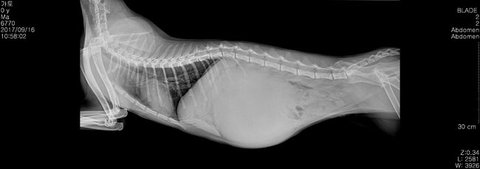

문제는 가토가 여자아이라 중성화하는데 위험할수도 있다고해서 엑스레이 찍었는데..

세상에 너무 깜짝놀랐어요.. 배가 2/3이 뭔가 혹?같은게 했어서요

(털에 가려있어서 잘 몰랐는데 찍고보니 무서웠어요 ㅜㅜ)

가토는 근육이 적당한편이래요 체중도 정상

혹같은게 몸통보다크죠..

배 홀쭉한거 보세요 ㅜㅜ